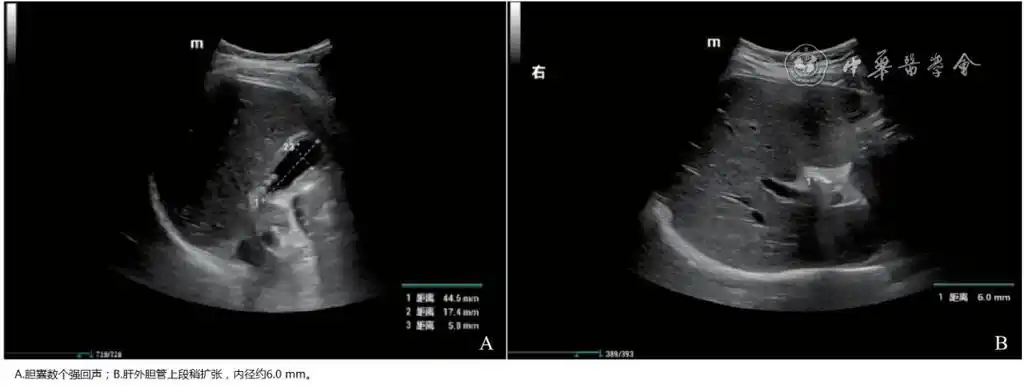

逆行胰胆管造影治疗儿童胆总管结石并发急性胰腺炎一例(附内镜下视频)

6 转归院外治疗1个月后复查腹部彩超及mrcp未见胆管增宽及结石,内镜下